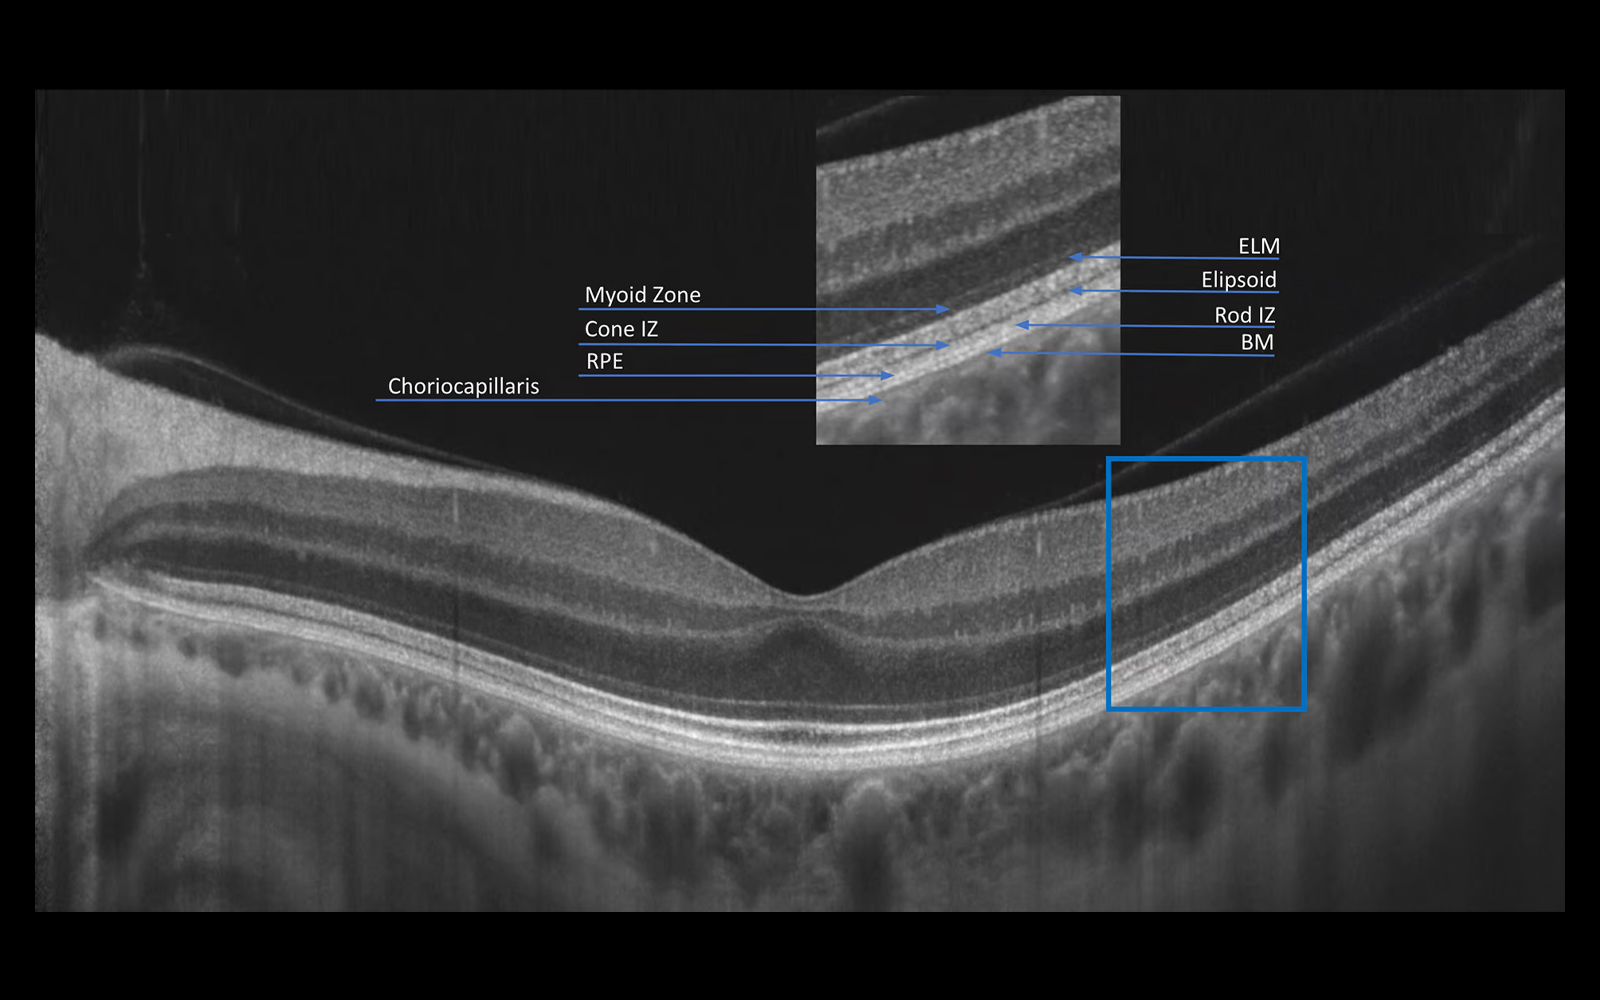

The system provides 3 µm resolution imaging, enabling detailed visualization of fine ocular structures and improved detection of subtle pathological changes.

The combination of super-fast scanning at 130,000 scans per second and 3 µm High Resolution will provide a powerful tool for optimising precision, accuracy and improving the detection of the smallest lesions in tissue.

With a unique combination of super-fast scanning at 130,000 scans per second and ultra-high 3 µm resolution, this powerful device takes precision, accuracy, and detection of even the finest lesions to a whole new level.

AI Retina

AI-based segmentation of the posterior segment enables automatic detection and analysis of up to 12 retinal layers, resulting in more accurate recognition of retinal layer boundaries. The AI system supports precise structural assessment and improves evaluation of pathological changes within the retina.